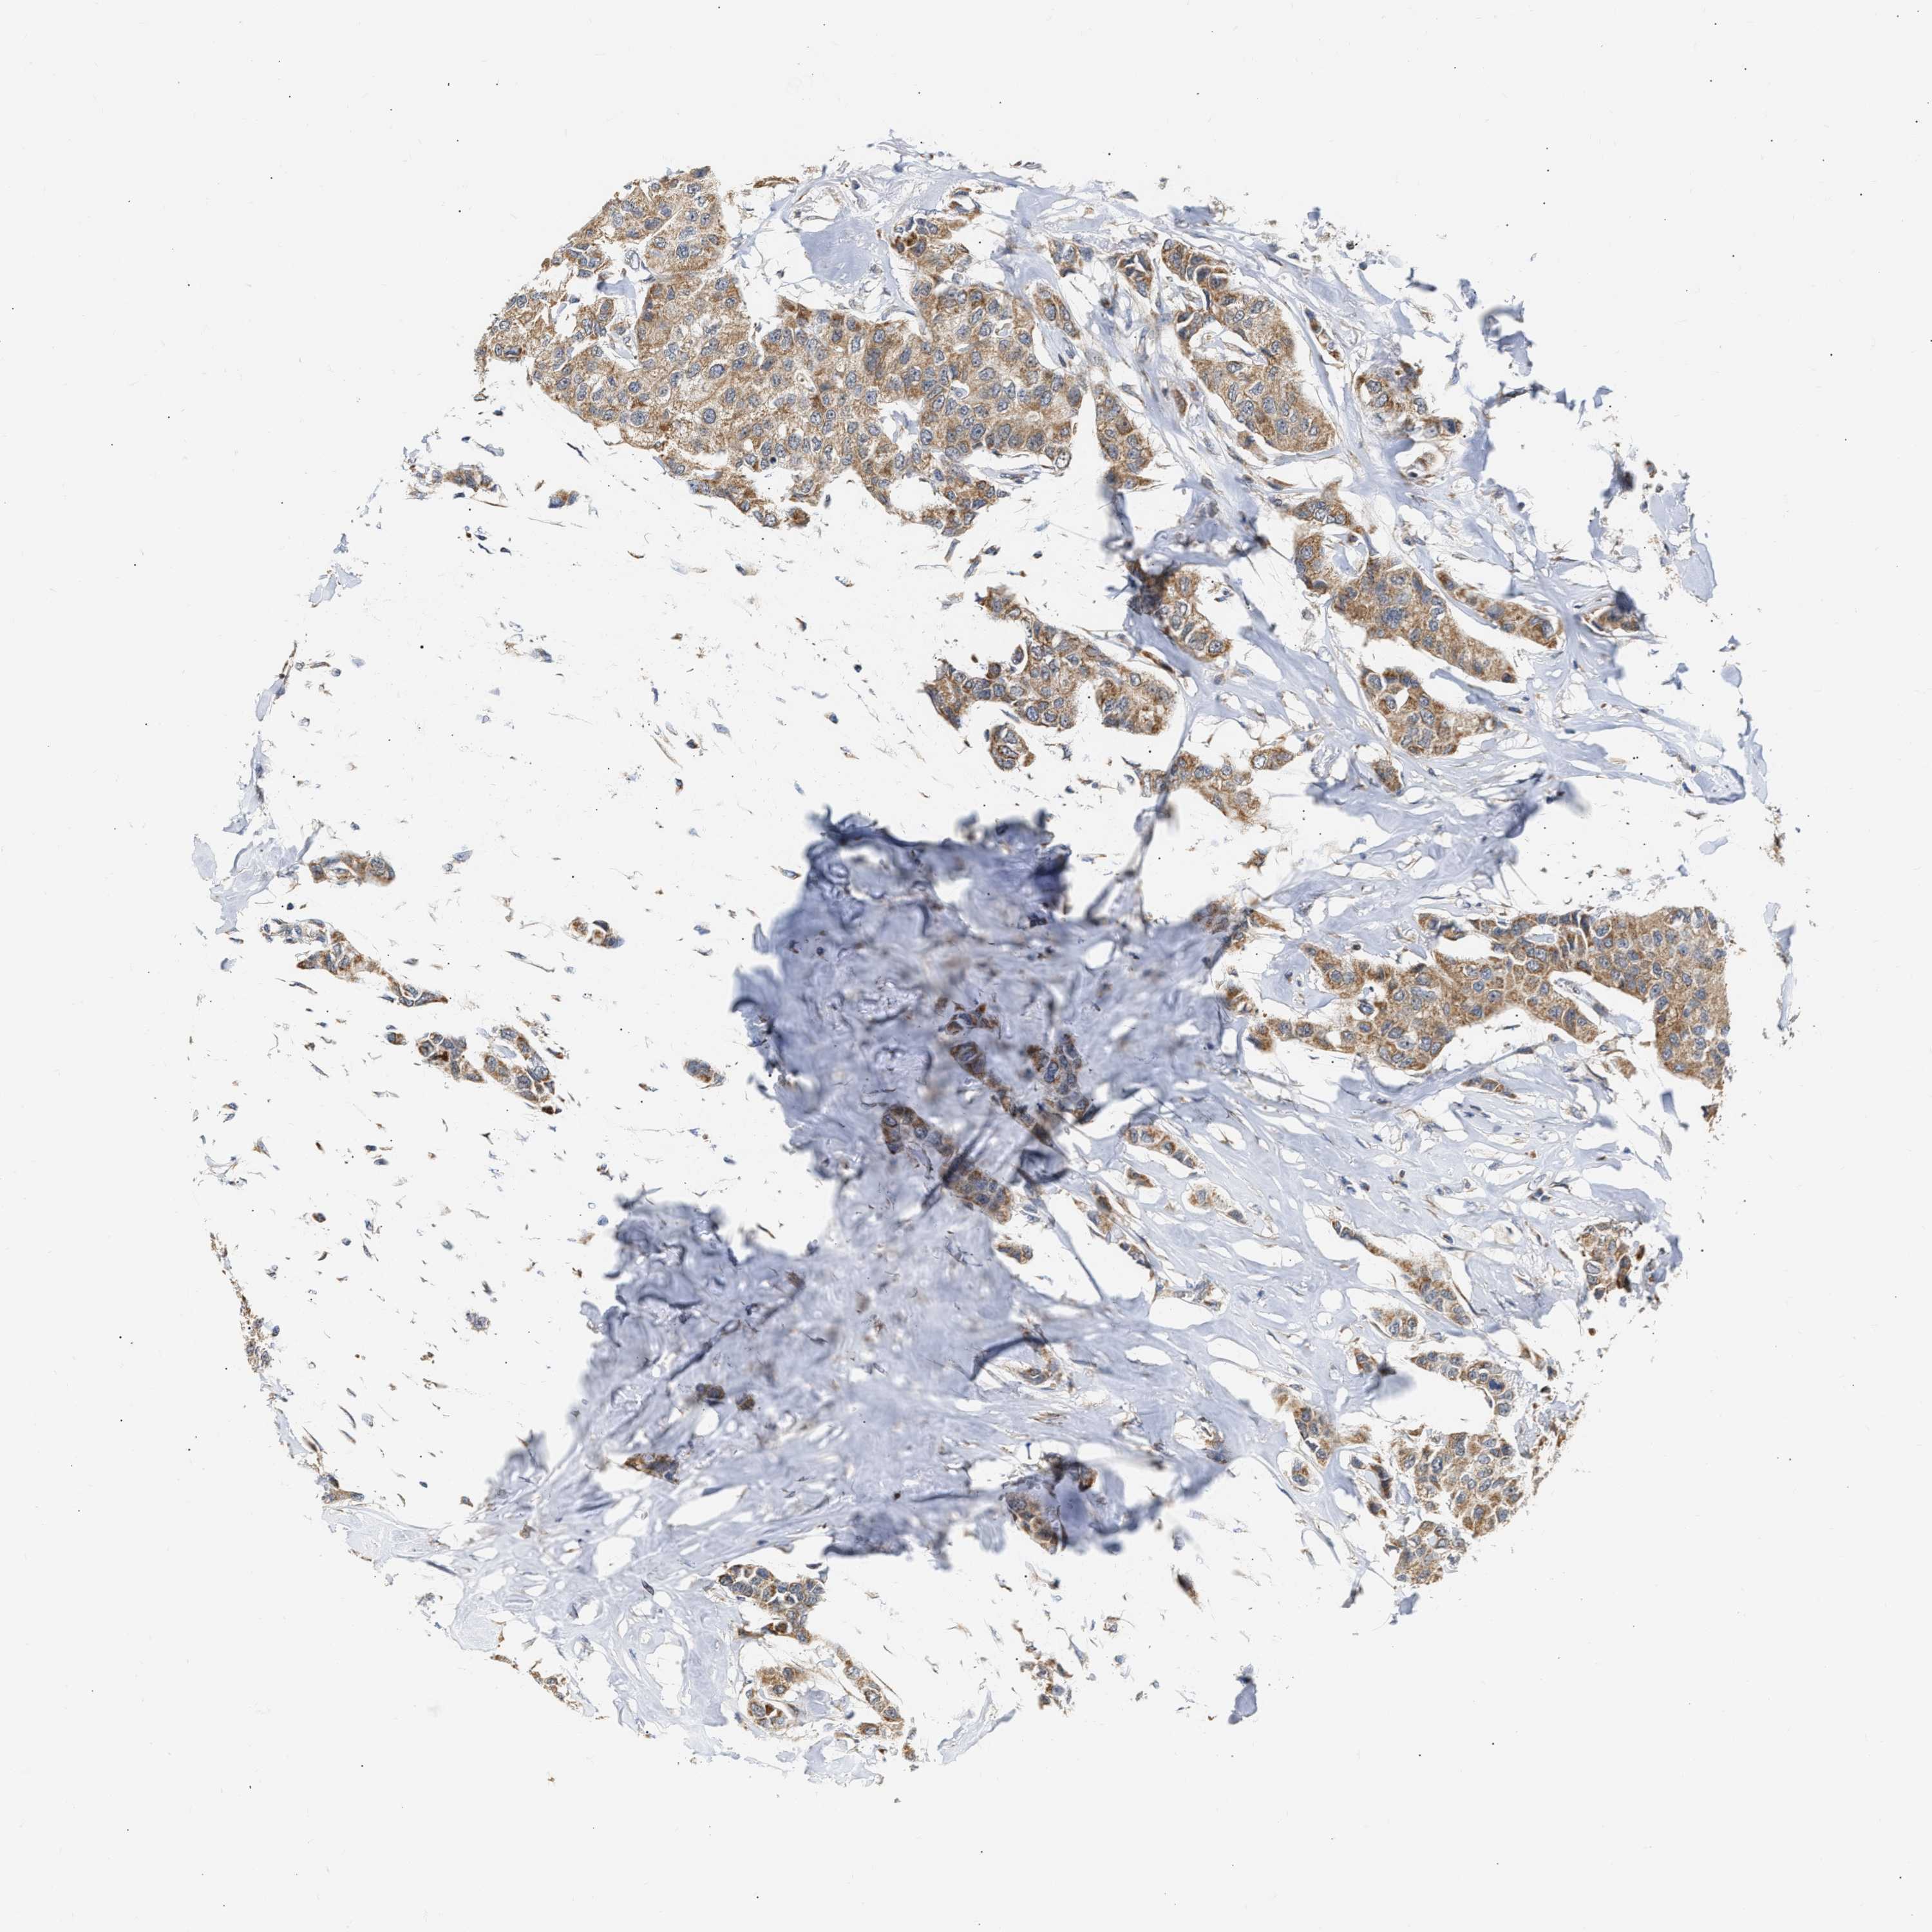

BRCA TCGA BRCA VALIDATION PROTEIN EXPRESSION